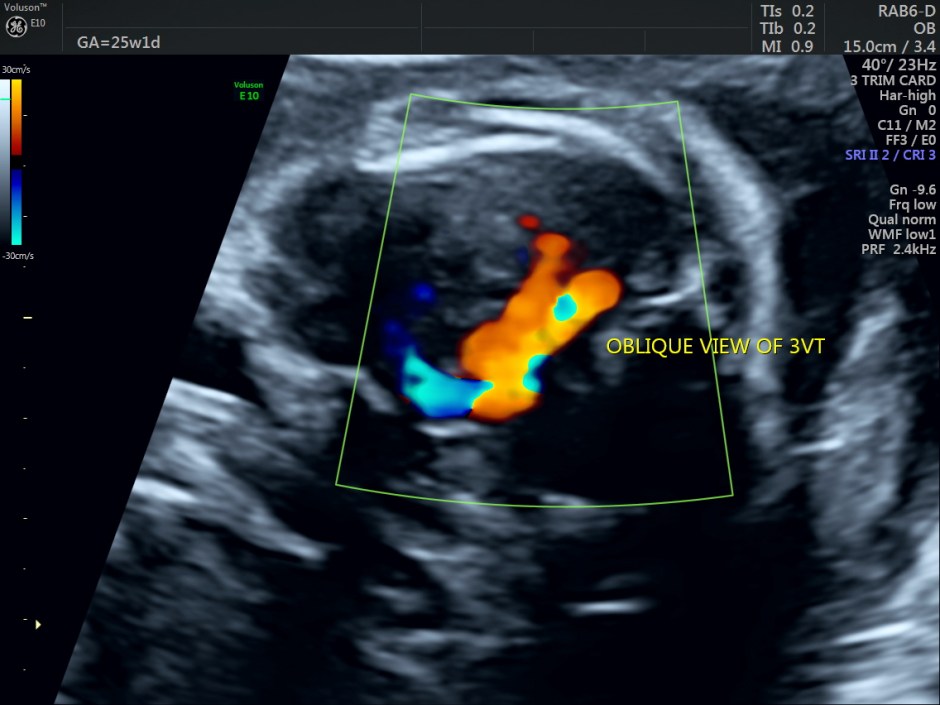

This was a 25-year-old primi referred for a 2nd opinion for Double Outlet Right Ventricle. No VSD was detected by the sonologist.

This fetus showed left heart dysplasia, a small VSD and Double Outlet Right Ventricle with malposition of the great arteries.

The right ventricular outflow is seen in this picture.